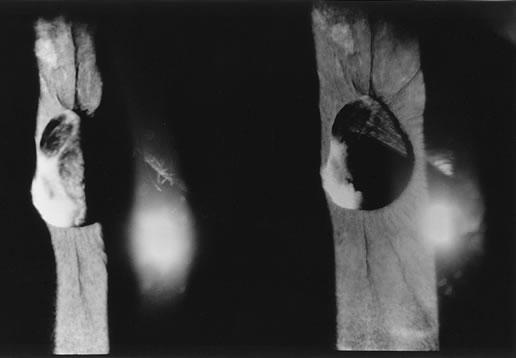

The Nd:YAG laser provides the ophthalmologist with the ability to open the posterior lens capsule without making a surgical incision. Because of this, the risk of infection and of complications related to making the incision and introducing instruments into the vitreous are reduced. In older cooperative children, the procedure can be performed in an office setting (Fig. 3).